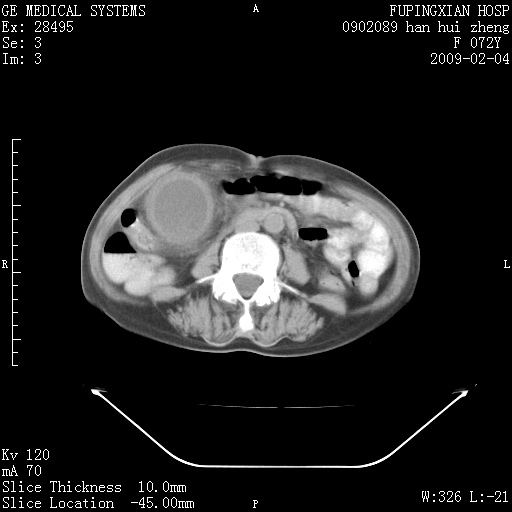

标题: CT17930:F72Y,右腹部包块5日,脐右扪及一包块,触痛。 [打印本页]

标题: CT17930:F72Y,右腹部包块5日,脐右扪及一包块,触痛。

胆囊增大,虽然内壁光滑,但囊壁不均匀性增厚,胆囊窝积液,所以首先考虑胆囊炎,但并不能排除胆囊癌的可能。诊断胆囊癌的依据是:胆囊壁呈不均匀性明显增厚,部分层面胆囊与肝脏界限不清。